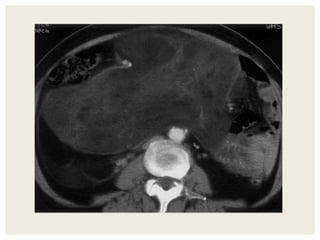

 55 yr old female patient

 Presented with complaints of lump abdomen and vague

abdominal discomfort

 Bowel habits normal with no other gastrointestinal complaints

CASE 2

DIFFERENTIALS

• Retroperitoneal sarcomas

Leiomyosarcoma

Undifferentiated liposarcoma

Malignant fibrous histiocytoma

• Exophytic Gastrointestinal stromal tumor